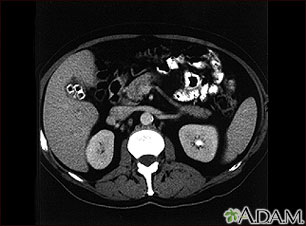

Imaging tests can show gallstones or inflammation. You may have one or more of these tests: